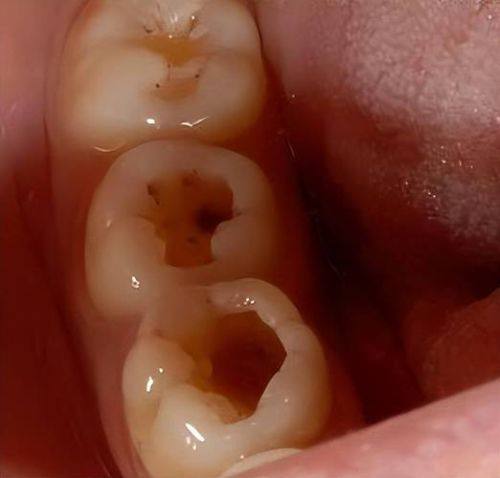

浅龋齿是龋齿发展的更初阶段。在这个时期,病变通常只局限于牙齿的表层,也就是牙釉质。从外观上看,牙齿表面可能会出现一些细微的变化。在浅龋齿的图片中,我们可以看到牙齿表面可能会有白色或黄褐色的斑点。这些斑点可能不太明显,特别容易被忽视。但仔细观察,会发现这些区域的牙齿光泽度与正常牙齿有所不同。

浅龋齿一般不会引起疼痛,患者通常没有明显的自觉症状。但如果不及时发现和处理,细菌会继续侵蚀牙齿,病情就会逐渐加重。所以,定期查看浅龋齿的症状图片,有助于我们在早期发现问题。

早期龋齿除了浅龋齿的表现外,还可能有其他一些特征。随着病情的发展,牙齿表面的斑点可能会逐渐扩大,颜色也会变得更深。在早期龋齿的图片中,我们能看到牙齿表面可能会出现一些小的龋洞,虽然这些龋洞还比较浅,但已经是龋齿进一步发展的信号。

此时,患者可能会在吃冷热酸甜食物时,感觉到牙齿有轻微的敏感。这种敏感可能只是短暂的,但也提示我们牙齿已经出现了问题。通过早期龋齿的图片,我们可以更清晰地认识到这些症状,及时关注口腔健康。